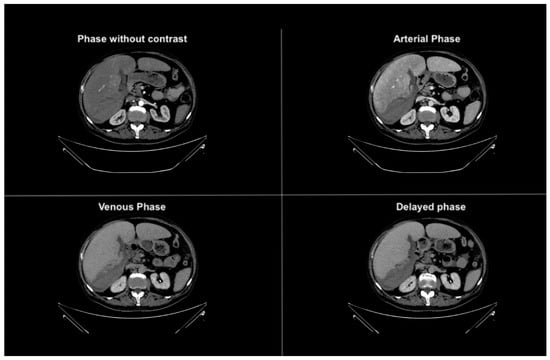

Figure 1. Axial phases without and with contrast CT images demonstrating hepatomegaly with a liver length of approximately 25 cm. The liver parenchyma displays a finely and diffusely heterogeneous density.